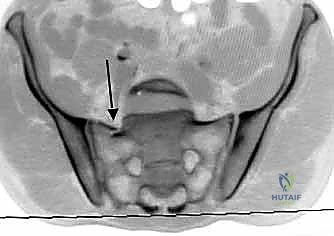

4. التصوير بالرنين المغناطيسي (MRI): يُستخدم في حالات الاشتباه بوجود إصابات عصبية دقيقة أو تمزقات في الأربطة المعقدة.